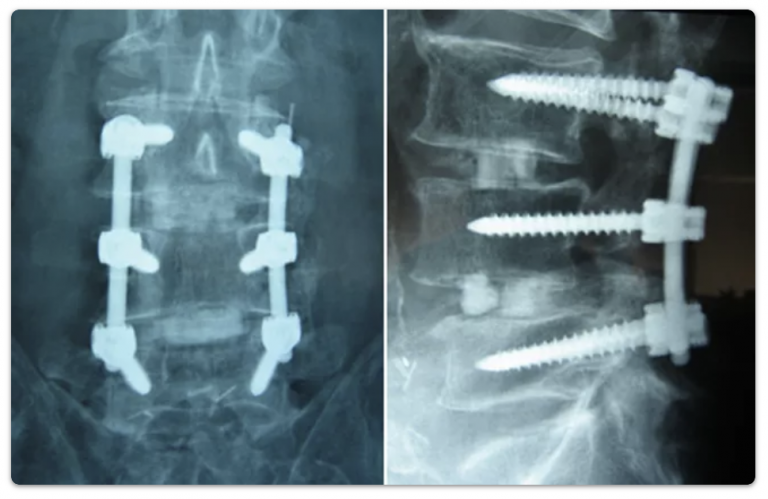

Ancak nörojenik kladikasyon dediğimiz hastanın zamanla yürüyüş mesafesinin azalması ve beraberinde bacaklarda kramp ve kasılma varsa, bacaklarda kuvvet kaybı varsa, idrar torbası ile bağırsak problemi gelişmiş ve hastanın yaşam kalitesinin düştüğü durumlarda cerrahi tedavi uygulanmalıdır. Cerrahi tedavi günümüzde gelişmiş teknolojik olanaklarla ve özellikle ameliyat mikroskobunun beyin cerrahisi pratiğinde kullanılırlığının artmasıyla daha konforlu ve başarılı yapılır hale gelmiştir. Cerrahide amacımız omurilik kesesi ve içindeki sinirlere olan basının kaldırılmasıdır. Bu ameliyatın tıp literatüründeki adı, lomber dekompresyon ameliyatıdır. Omurganın arka çatısını oluşturan her iki yandaki kemikler ve sarı bağ dokusu alınarak omurilik kesesi rahatlatılır. Uygun olan olgularda ise omurganın sağlamlığını daha fazla bozmamak için bir taraftan yaklaşım yapılır, yani omurganın arkasında bir taraftan kemik doku çıkarılır ancak her iki tarafta da mikroskop altında genişletme ameliyatı yapılır. Bel omurilik kanalı daralması ileri dejeneratif bir süreç olduğundan hastaların bazılarında omurların birbiri üzerinde kayması söz konusu olabilir. Bazen de darlık ileri derecede olup tek ya da iki taraflı sınırlı rahatlatma yeterli olmayıp tüm arka kemik çatının ve faset eklemlerin alınması gerekebilir. Bu durumlarda omurilik gevşetme ameliyatına ek olarak hastanın omurlarının sabitlenmesini sağlayan vida, kafes uygulaması gerekebilir. Ancak bu tüm hastalara vida-kafes uygulaması gerektiği anlamına gelmemektedir. Hastalar ameliyat sonrası dönemde bel sağlıklarına dikkat etmeli ve bel ağrısı yaratacak aktivitelerden sakınmalıdır. Gelecekteki bel sağlığını etkileyen diğer 2 önemli etken ise önerilen egzersiz programlarına sürekli devam etmek ve kilo almamaya özen göstermektir.

Ancak nörojenik kladikasyon dediğimiz hastanın zamanla yürüyüş mesafesinin azalması ve beraberinde bacaklarda kramp ve kasılma varsa, bacaklarda kuvvet kaybı varsa, idrar torbası ile bağırsak problemi gelişmiş ve hastanın yaşam kalitesinin düştüğü durumlarda cerrahi tedavi uygulanmalıdır. Cerrahi tedavi günümüzde gelişmiş teknolojik olanaklarla ve özellikle ameliyat mikroskobunun beyin cerrahisi pratiğinde kullanılırlığının artmasıyla daha konforlu ve başarılı yapılır hale gelmiştir. Cerrahide amacımız omurilik kesesi ve içindeki sinirlere olan basının kaldırılmasıdır. Bu ameliyatın tıp literatüründeki adı, lomber dekompresyon ameliyatıdır. Omurganın arka çatısını oluşturan her iki yandaki kemikler ve sarı bağ dokusu alınarak omurilik kesesi rahatlatılır. Uygun olan olgularda ise omurganın sağlamlığını daha fazla bozmamak için bir taraftan yaklaşım yapılır, yani omurganın arkasında bir taraftan kemik doku çıkarılır ancak her iki tarafta da mikroskop altında genişletme ameliyatı yapılır. Bel omurilik kanalı daralması ileri dejeneratif bir süreç olduğundan hastaların bazılarında omurların birbiri üzerinde kayması söz konusu olabilir. Bazen de darlık ileri derecede olup tek ya da iki taraflı sınırlı rahatlatma yeterli olmayıp tüm arka kemik çatının ve faset eklemlerin alınması gerekebilir. Bu durumlarda omurilik gevşetme ameliyatına ek olarak hastanın omurlarının sabitlenmesini sağlayan vida, kafes uygulaması gerekebilir. Ancak bu tüm hastalara vida-kafes uygulaması gerektiği anlamına gelmemektedir. Hastalar ameliyat sonrası dönemde bel sağlıklarına dikkat etmeli ve bel ağrısı yaratacak aktivitelerden sakınmalıdır. Gelecekteki bel sağlığını etkileyen diğer 2 önemli etken ise önerilen egzersiz programlarına sürekli devam etmek ve kilo almamaya özen göstermektir.

Bu basının kaldırılması önden veya arkadan yapılacak ameliyatlarla mümkündür. Ancak hangisinin daha uygun olacağı kararı, yapılacak incelemeler sonrası beyin ve sinir cerrahisi uzmanınca verilir. Önden yapılan ameliyatlarda basıyı sadece disk oluşturuyorsa, o diske komşu iki omurgaya herhangi bir girişim yapmadan sadece diske yönelik cerrahi yapılabilir. Bazen önden bası oluşturan yapı omurların arkasında uzanan oldukça kuvvetli bir bağın kireçlenmesi olabilir. Bu durumda etkilenen seviye boyunca omurga gövdesi/gövdeleri ile disk dokusu çıkarılır. Yerine kemik greft veya omurga yerine geçecek kafes görünümlü protez materyal yerleştirilir. Daha sonra da önden plak ve vidalarla sabitleme işlemi (füzyon) yapılır. Ancak bu tüm hastalara vida-kafes uygulaması gerektiği anlamına gelmemektedir.

Arkadan yapılan ameliyatlarda, basıyı oluşturan sarı bağ ve omurganın arka tarafını oluşturan çatının (lamina) tamamen çıkarılması gerekebilir. Bu durumda omurgayı güçlendirmek amacıyla omurgaya vida ve bunları tutan çubuklar koyarak sabitleme (füzyon) ameliyatının yapılması uygun olacaktır. Laminanın bir parçası çıkarılıp kesilip ayrılması sonrası araya konulan protez malzemenin yardımıyla uygulanan laminoplasti ameliyatı ile de omurilik kanalı genişletilmesi mümkündür.